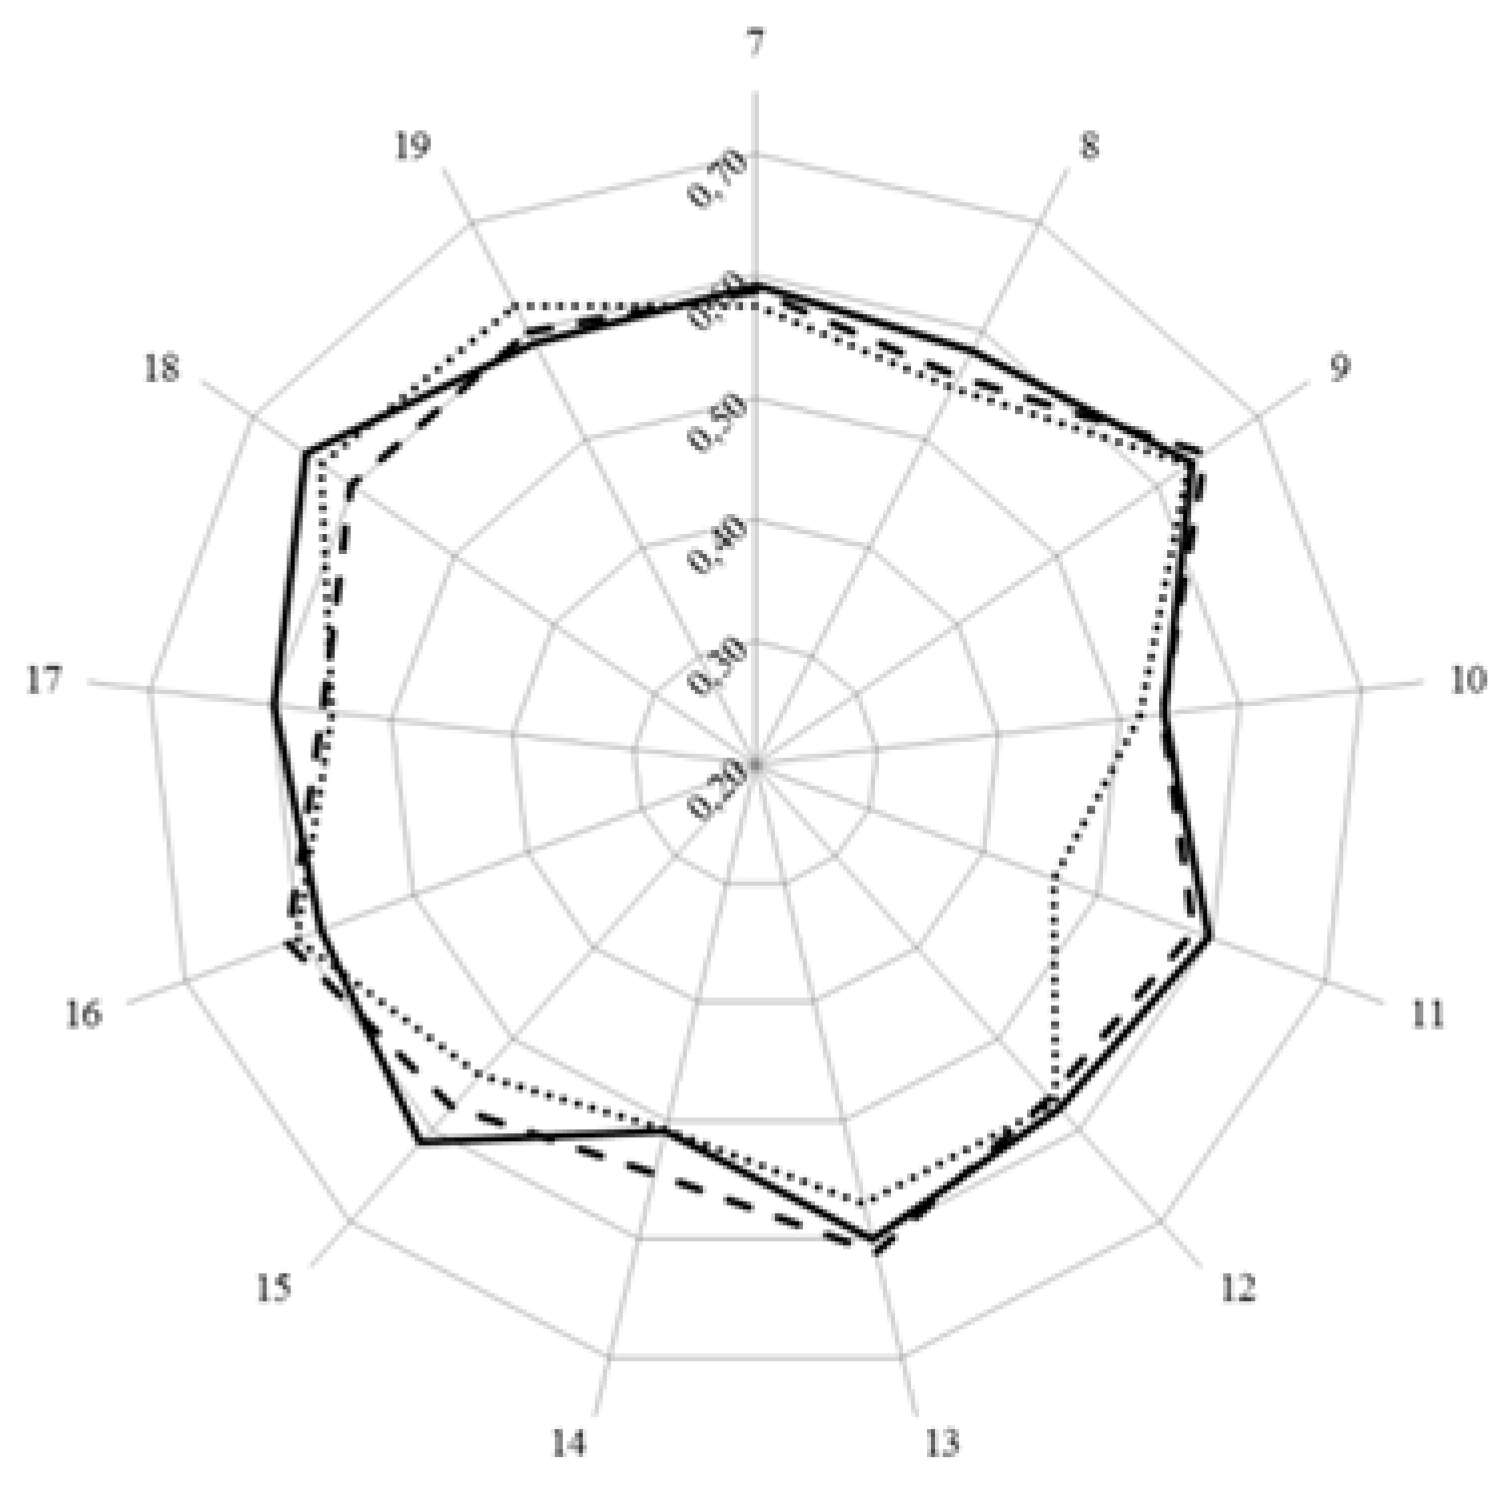

- < 0.2 poor,

- 0.21 – 0.4 fair,

- 0.41 – 0.6 moderate,

- 0.61 – 0.8 substantial,

- > 0.81 good.

3. Results and Discussion

| Score (%) | 77.4 | 78.3 | 77.9 | |||

| Leik ordinal consensus | 0.59 | 0.55 | 0.58 | |||

| Cluster 7. Personal competences: learning and knowledge. | 1 | Ability to identify learning needs and to learn independently (including continuous professional development (CPD)). | 84.5 | 93.7 | 15.7 | 89.8 | 13.1 |

| 2 | Analysis: ability to apply logic to problem solving, evaluating pros and cons and following up on the solution found. | 88.8 | 94.5 | 7.5 | 91.1 | 3.6 | |

| 3 | Synthesis: capacity to gather and critically appraise relevant knowledge and to summarise the key points. | 85.1 | 92.8 | 10.8 | 87.9 | 4.0 | |

| 4 | Capacity to evaluate scientific data in line with current scientific and technological knowledge. | 76.5 | 87.3 | 18.5 | 75.8 | 0.4 | |

| 5 | Ability to interpret preclinical and clinical evidence-based medical science and apply the knowledge to pharmaceutical practice. | 86.0 | 81.2 | 5.2 | 75.9 | 17.3 | |

| 6 | Ability to design and conduct research using appropriate methodology. | 60.6 | 65.4 | 4.9 | 40.2 | 34.3 | |

| 7 | Ability to maintain current knowledge of relevant legislation and codes of pharmacy practice. | 81.7 | 86.3 | 3.3 | 91.7 | 25.7 | |

| Cluster 8. Personal competences: values. | 8 | Demonstrate a professional approach to tasks and human relations. | 86.6 | 91.5 | 7.7 | 94.5 | 23.3 |

| 9 | Demonstrate the ability to maintain confidentiality. | 85.4 | 92.3 | 22.8 | 95.3 | 50.6 | |

| 10 | Take full personal responsibility for patient care and other aspects of one’s practice. | 84.4 | 88.3 | 3.2 | 94.8 | 24.9 | |

| 11 | Inspire the confidence of others in one’s actions and advice. | 77.8 | 83.8 | 8.9 | 88.8 | 13.0 | |

| 12 | Demonstrate high ethical standards. | 85.3 | 95.3 | 43.4 | 95.2 | 24.6 | |

| Cluster 9. Personal competences: communication and organisational skills. | 13 | Effective communication skills (both orally and written). | 91.2 | 93.5 | 3.9 | 94.8 | 4.0 |

| 14 | Effective use of information technology. | 81.1 | 83.8 | 1.4 | 86.1 | 3.8 | |

| 15 | Ability to work effectively as part of a tea. | 86.4 | 83.3 | 6.1 | 89.2 | 1.1 | |

| 16 | Ability to identify and implement legal and professional requirements relating to employment (e.g., for pharmacy technicians) and to safety in the workplace. | 74.8 | 77.9 | 1.9 | 81.0 | 4.5 | |

| 17 | Ability to contribute to the learning and training of staff. | 73.5 | 79.6 | 6.6 | 82.5 | 6.6 | |

| 18 | Ability to design and manage the development processes in the production of medicines. | 61.2 | 60.0 | 0.8 | 43.2 | 38.0 | |

| 19 | Ability to identify and manage risk and quality of service issues. | 77.5 | 76.1 | 4.0 | 79.2 | 2.3 | |